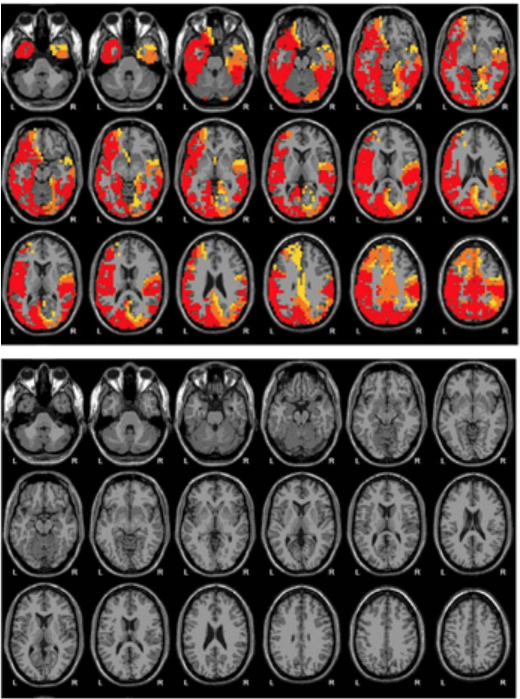

Brain scans from Emerald show what it claims to be before (top) and after (bottom) images of a woman’s brain following NAD treatment. The images appear in an Emerald brochure, including text that says, “The brain is more calm after 12 days of NAD+ Amino Acids Therapy.”(Emerald/Screenshot by Side Effects Public Media)

For an additional $400 fee, Emerald patients can have their brain scanned at a nearby clinic to document their progress with NAD therapy. An Emerald brochure shows a series of scans from a woman whose “brain is suffering from alcoholism.” Areas that glow red, orange and yellow — “HYPERACTIVE and OVERACTIVE” — totally disappear from the scans after 12 days of NAD therapy, according to the company.

“This is totally bogus,” says Leslie Hulvershorn, an addiction psychiatrist at the Indiana University School of Medicine with expertise in brain imaging who reviewed the images via email. “We do not have research in our field that allows us to use EEG or any other brain imaging technique to document treatment response.”